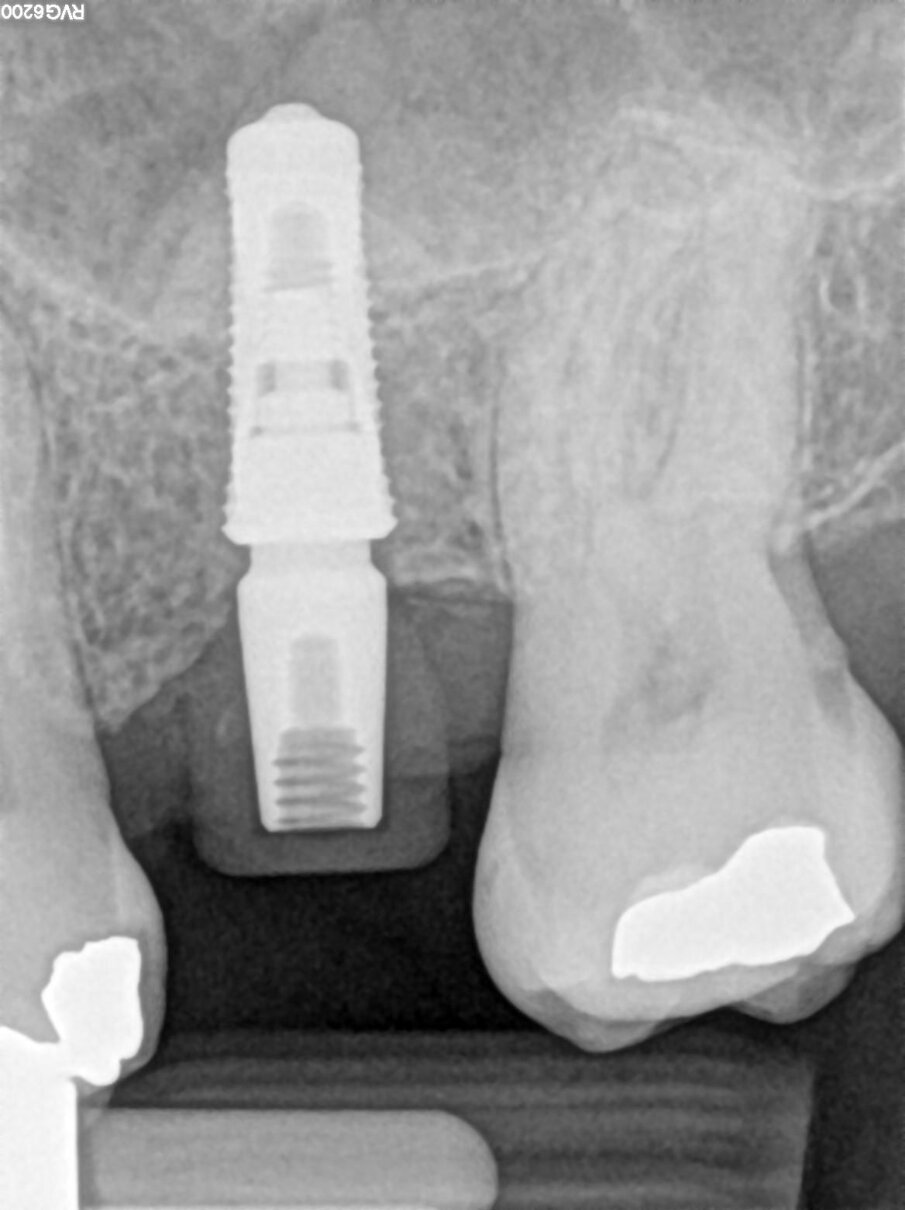

Un paziente con altezza ossea residua di 6 mm nella regione mascellare posteriore è stato sottoposto a un intervento di rialzo di seno per via transcrestale (Figg. 1, 2).

È stato inserito un impianto tronco-conico di 10 mm di lunghezza e 4,2 mm di diametro (AoN SLC con connessione Revcon) con torque di inserzione di 35 N e valori di ISQ pari a 66 in direzione vestibolo-linguale e 68 in direzione mesio-distale20. È stato applicato un moncone conometrico dritto e avvitato a 35 N con relativa cappa di guarigione in peek21 (Figg. 4, 5).

Fig. 6_Radiografia post-operatoria.